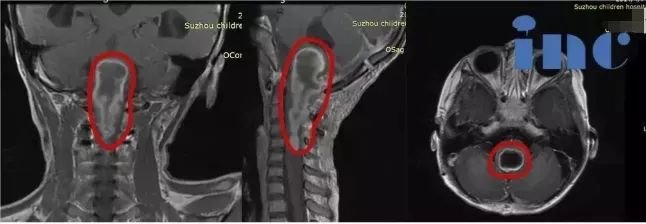

18歲的帆帆,自2009年起便走上了一條充滿挑戰(zhàn)的求醫(yī)之路。4歲那年,他接受了第一次手術,切除了頭頂的神經鞘瘤。14歲時,確診神經纖維瘤病2型,進行了右側小腦病損切除術。2022年10月以來,帆帆反復出現右下肢劇痛,嚴重時疼痛可持續(xù)約6小時,難以入睡;還伴有進行性聽力下降的困擾。今年7月的復查顯示,其后顱窩、頸椎椎管及胸壁多處病灶仍有進展,右頸部病變大小約7.0cmx5.2cm。面對疾病的反復考驗,這個少年有著超乎年齡的堅韌,而他的家人始終是他最堅強的后盾,用不離不棄的陪伴給予他前行的力量。

在咨詢巴教授后,他們了解到需要分次手術應對多處病灶。由于頸髓病灶持續(xù)進展可能面臨癱瘓風險,首次手術將優(yōu)先處理該部位。面對面交流,教授的回復給予了他們極大的信心,更賦予了他們決策的勇氣。

影像